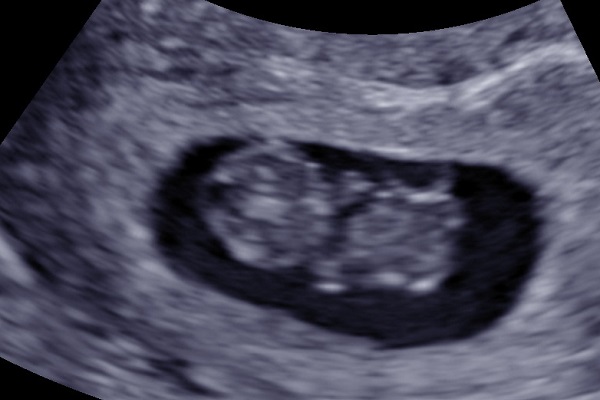

9 Weeks Pregnant: Baby Growth & What to Expect